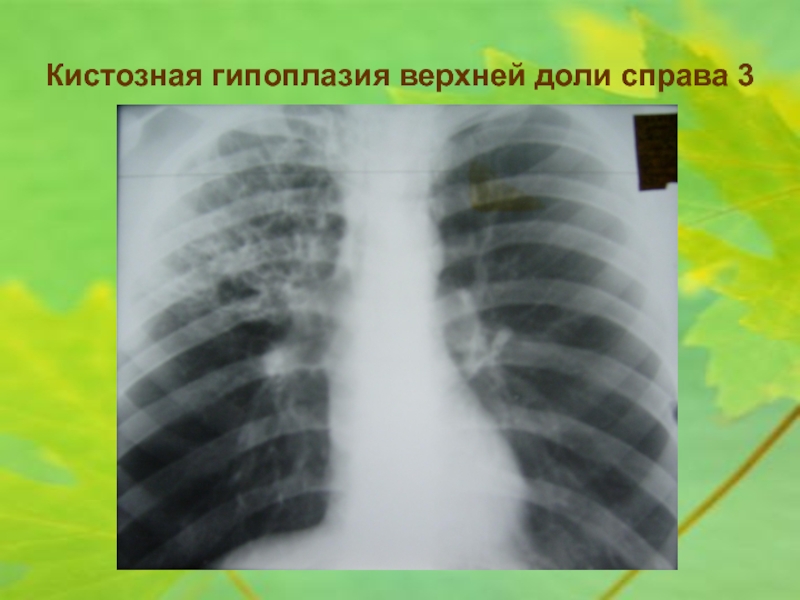

Рентгеновские снимки при врожденной эмфиземе легкого

Раздел: Визуальные уроки